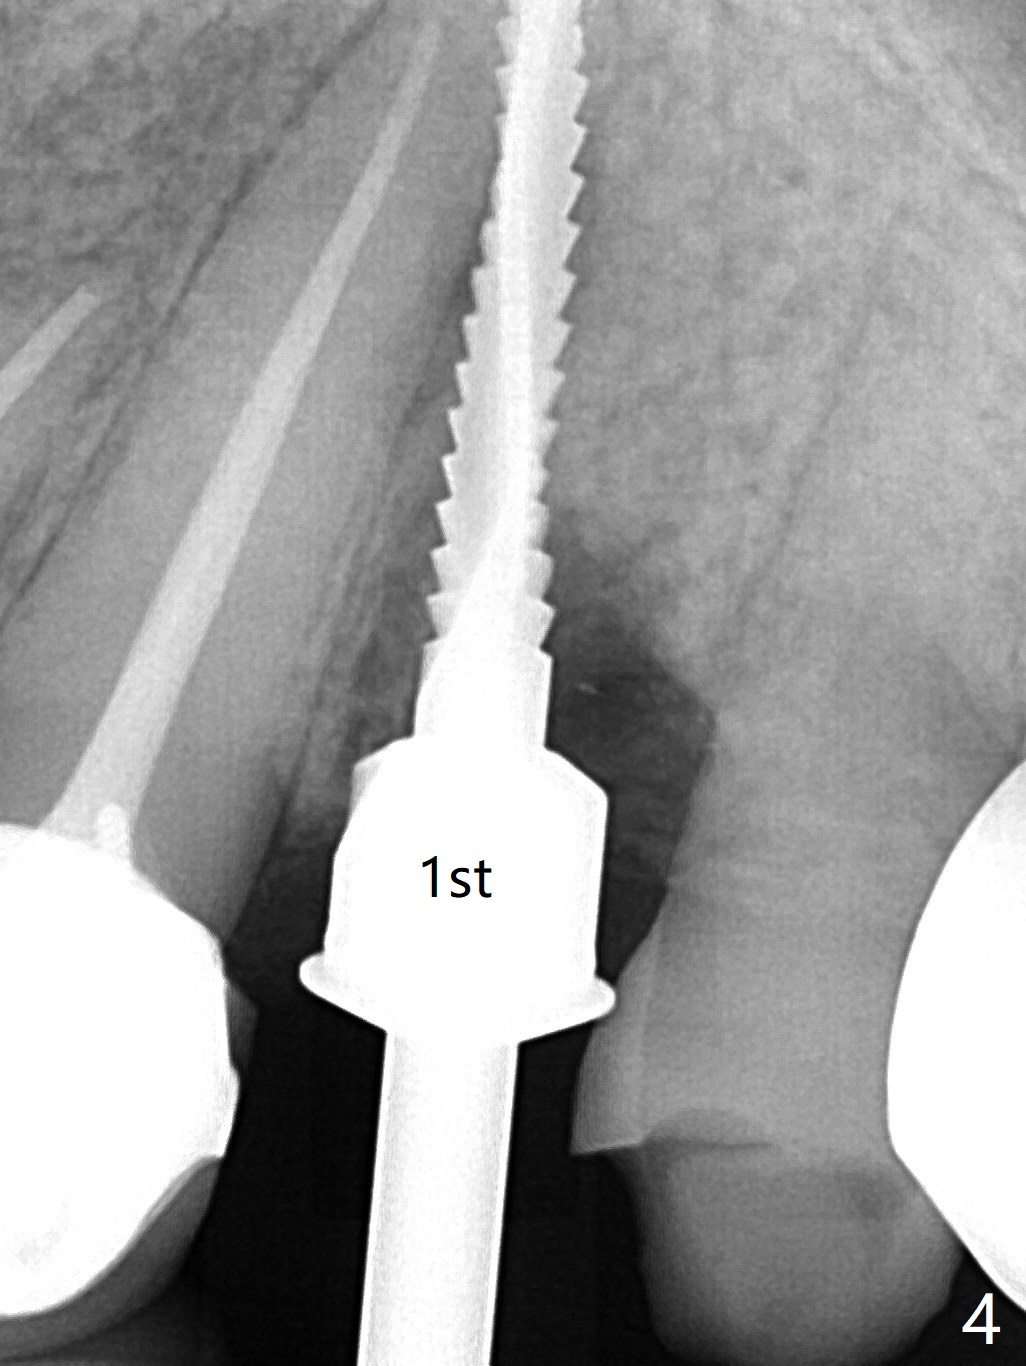

68岁女左上4颊侧瘘道(图一:*),与根尖颊侧骨板缺失相通,其实腭侧根尖周围病变更大(也与颊侧窝相通),术中没有注意腭侧根接近3(图二:P),稀里糊涂的基本顺着腭侧根(颊侧)走向钻洞(图四,与图三理想方向对比),突然记起术前设计钻洞必须在腭侧牙槽窝远中颊侧,在远中建立新洞眼(图五),之后无法再次建立新洞眼,只好利用同一个侧面切割钻头将钻洞往远中移位,同样效果不佳(图六),最后只好放弃,放置粘性骨粉(图七:*),覆盖PRF膜,6个月胶原膜,PGA缝线,牙周胶水。术后重新分析表明顺着腭侧牙槽窝种植与尖牙还是有分离(图八,九:*),因为牙槽窝是斜型的(图十:黑色),不过离颊侧骨板也接近(图八:B)。所以钻洞必须斜型针对远中骨壁,表浅些(图十一:红色箭头);一旦进入骨板,改变角度(图十二:红色箭头),适当矫枉过正,随着植体增大,钻洞会往近中偏移(白色箭头)。最好植体方向理想(图十三)。不过植骨后钻洞偏移可能性比较少。缝线和牙周胶水似乎是一个稳妥固定胶原膜方法。术后病人抱怨水肿严重,术后八天颊侧根尖隆起是由于骨粉推出骨板之外(图十五,十六:*),上颌窦底板无意穿孔(^)伴有上颌窦膜(M)增厚,与术前对比(图十七:上颌窦窦腔清晰)。术后一个月6个月吸收膜不见了,大多数缝线已经脱落,最后两根缝线撤除后,牙槽窝开口已经关闭,好像主要成分是骨粉(图十八)。术后5个月牙槽嵴宽,角化龈也宽,好像可以植入4x11.5毫米植体(图十九)。